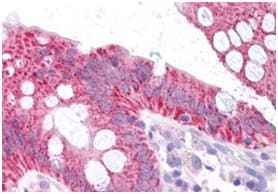

Anti-CDKN2A/p16INK4a antibody ab189034 is a rabbit polyclonal antibody that is used in CDKN2A/p16INK4a western blotting, IHC and immunofluorescence. Suitable for human and mouse samples.

Applications ICC/IF, IHC-P, WB